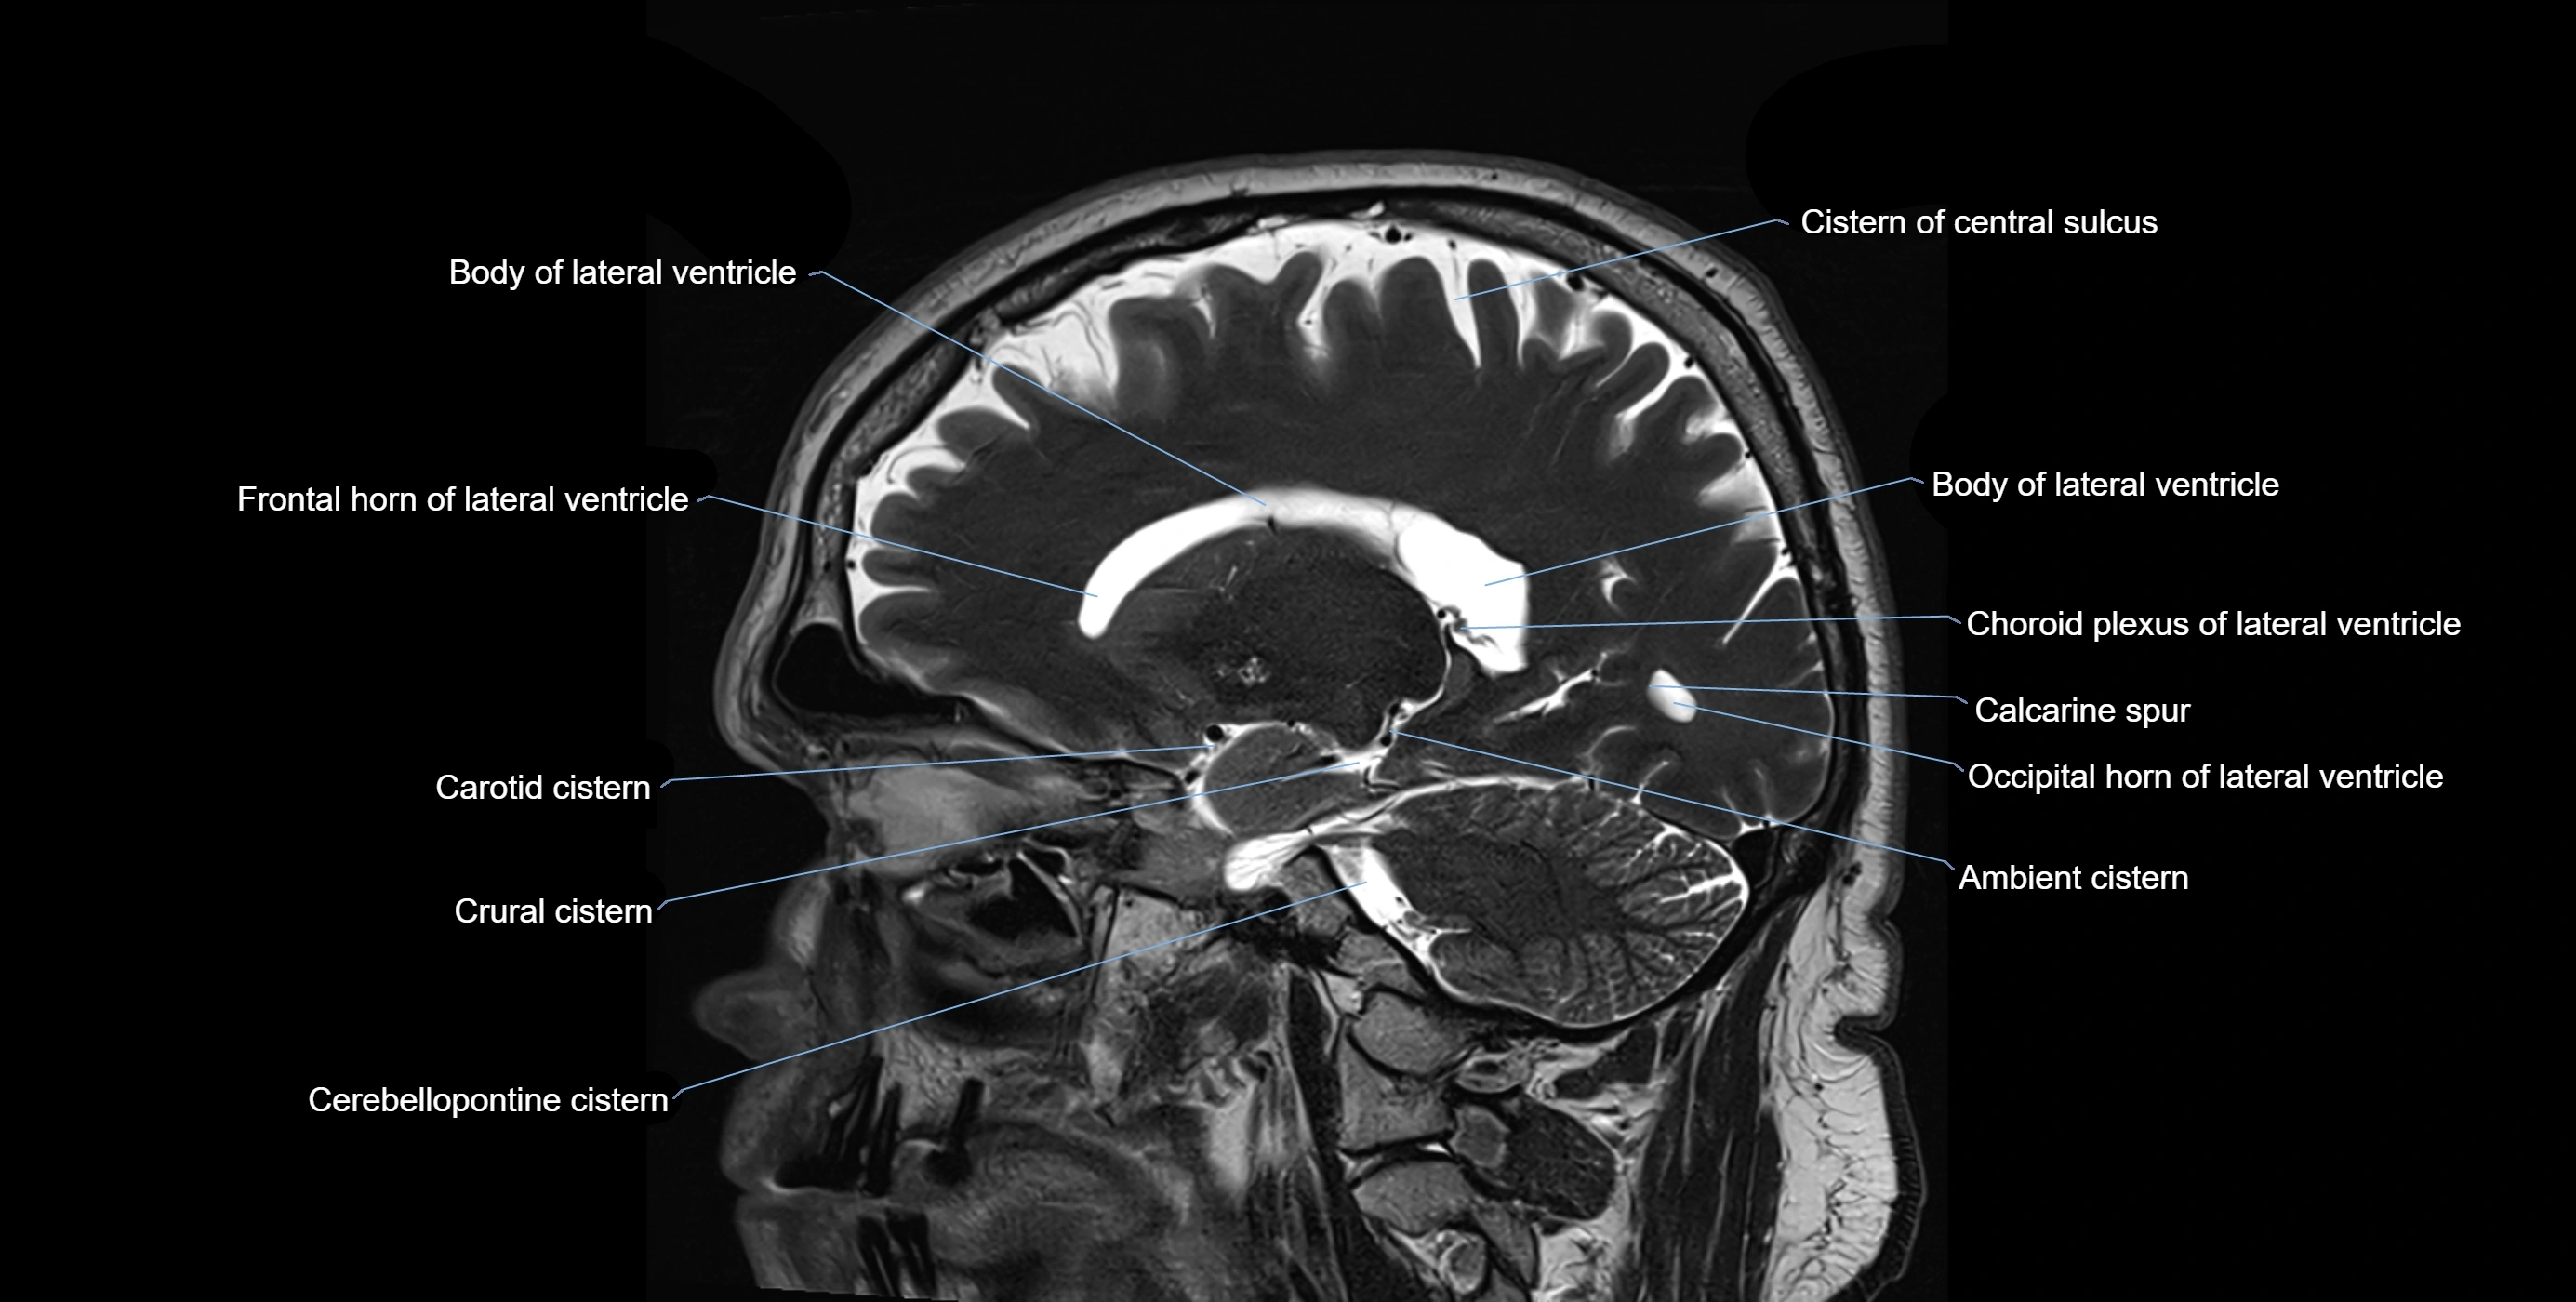

Ambient cistern

The ambient cistern is a paired, narrow, and elongated subarachnoid space located bilaterally along the lateral aspect of the midbrain. It serves as a conduit between the interpeduncular cistern anteriorly and the quadrigeminal cistern posteriorly. This cistern houses critical neurovascular structures, including parts of the posterior cerebral artery, superior cerebellar artery, trochlear nerve (cranial nerve IV), and the basal vein of Rosenthal. It plays an important role in the circulation of cerebrospinal fluid (CSF) and provides an anatomical corridor for various vessels and nerves passing around the midbrain.

MRI images

image